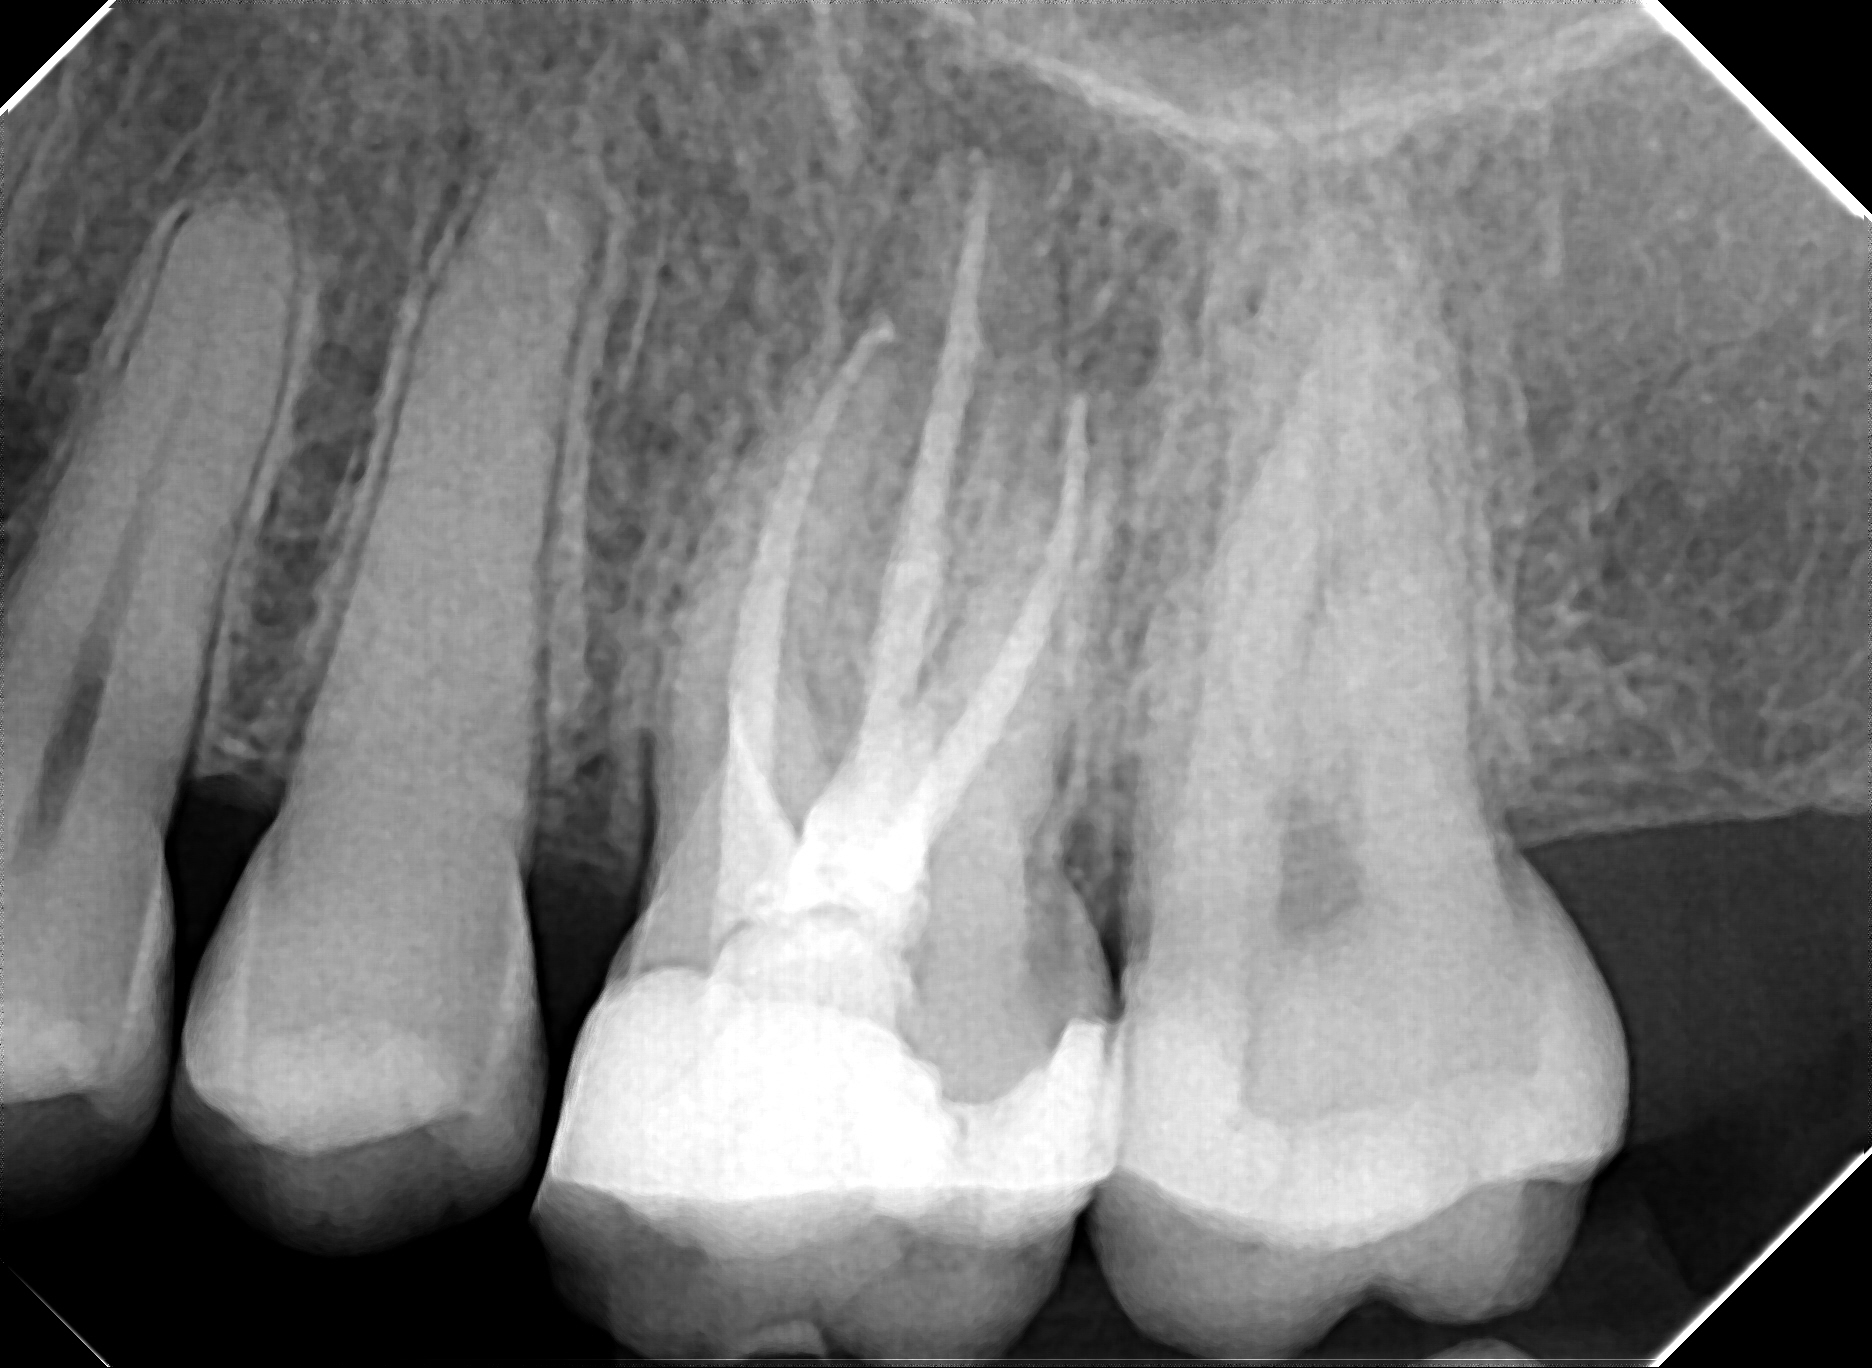

La situation la plus fréquente est l'apparition de douleurs dites spontanées, c'est à dire qui persistent sans qu'un élément externe à la dent soit nécessaire au déclenchement de cette douleur. Que ce soit suite à une carie proche de la partie "vivante" de la dent (la pulpe ou "nerf"), suite à un choc avec fracture de la dent, suite à un historique de soin volumineux (la dent est quasi-entièrement reconstruite par un composite ou un amalgame d'argent), l'apparition de ce type de douleur signifie que la pulpe dentaire a entamé un processus inflammatoire irréversible qui aboutira (ou a déjà abouti) à une nécrose pulpaire ( la dent est "morte") qui se transformera ensuite en infection pulpaire aiguë ou chronique ( "un abcès dentaire").

Un soin de base (type composite ou amalgame d'argent) serait insuffisant. Un traitement antibiotique ou anti inflammatoire ne peut qu'atténuer temporairement les douleurs, sans possibilité de guérison. Le traitement endodontique (traitement de canal) doit permettre de stopper la réaction inflammatoire et faire une désinfection complète de l'espace interne de la dent où se trouve la pulpe dentaire. L'objectif est de s'assurer que la dent ne puisse pas être un "réservoir" à bactéries en communication directe avec l'os de la mâchoire. On retrouve le principe nettoyer-désinfecter-sceller qui s'applique au traitement de toute carie dentaire, mais avec un équipement et des matériaux adaptés au contexte interne de la dent, bien plus complexe que celui des soins dentaires dits de base (composite ou amalgame d'argent).